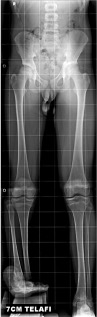

Tip 2 tibial hemimeli nedeni ile 13 yaşına kadar tedavi almamış hastaya uzaysal fiksatörle deformite düzeltme ve sonrasında da ayak bileği artrodezi uygulandı. Hasta plantigrade (düz ) basar hale getirildi.